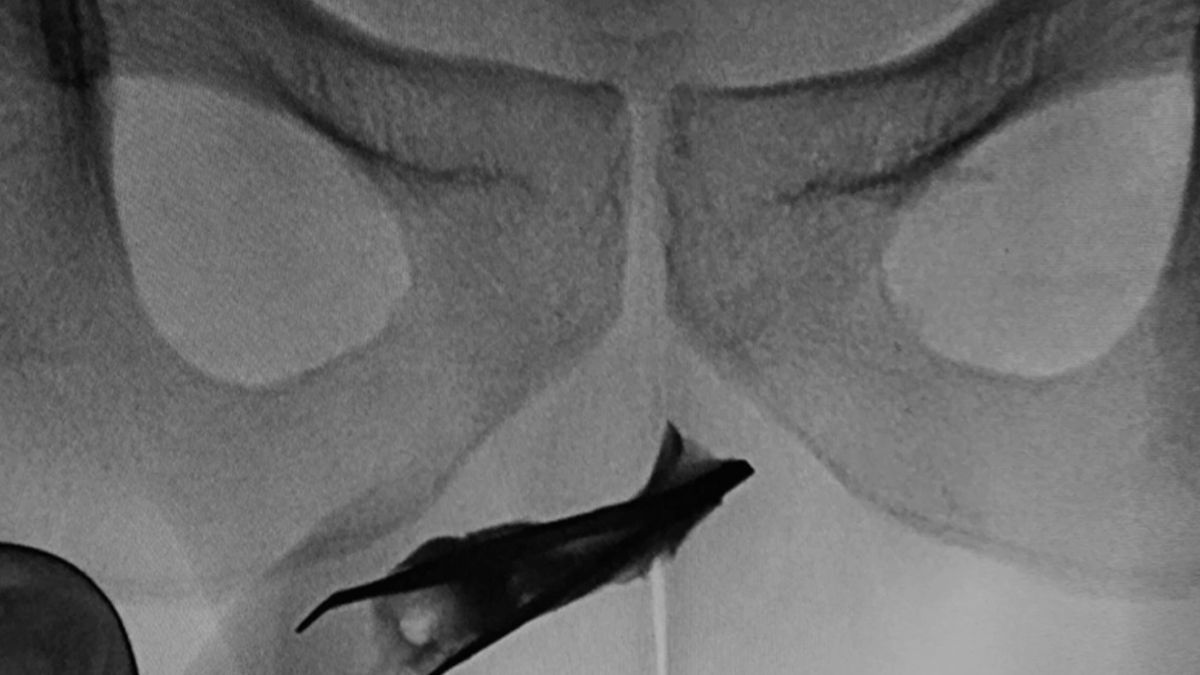

Un joven de 22 años fue intervenido en Arabia Saudita para extraer de su uretra una pinza de depilar de ocho centímetros que tenía introducidas desde hacía cuatro años, según informó el diario "Metro".

La pinza estaba abierta y había riesgo de que dañasen los órganos, aunque el paciente no presentaba síntomas de infección.

Por ello, según recoge la revista médica especializada 'Urology Case Reports', los médicos tuvieron que presionar el pene durante la operación para mantener las pinzas cerradas y poder así extraerlas satisfactoriamente.

El hombre aseguró que no había sufrido ningún dolor ni problemas a la hora de orinar durante los cuatro años que las pinzas permanecieron en su interior. Los médicos creen que se las introdujo para obtener placer sexual y recomendaron al paciente acudir al psicólogo, aunque este se negó.